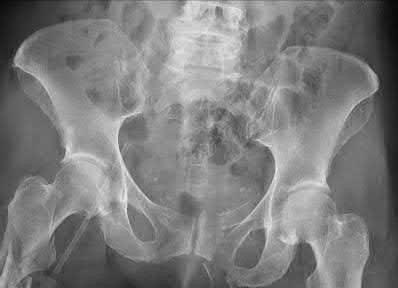

A 65-year-old female presents with the injury seen in Figures A and B after a motor vehicle collision. She is hemodynamically unstable and undergoes emergent pelvic supra-acetabular external fixation followed by laparotomy. She is now hemodynamically stable and cleared for surgery. She has no evidence of neurologic deficit on examination. Which of the following factors is a relative contraindication to open reduction and plating of her posterior pelvic injury from an anterior approach?

An anterior approach to the sacroiliac (SI) joint is indicated with displaced SI joint dislocations that cannot be reduced with closed or percutaneous techniques. One contraindication to anterior exposure of the SI joint is comminuted sacral fracture patterns.

Posterior pelvic ring injuries that are unable to be reduced by closed techniques may require open reduction via anterior or posterior approaches. Relative contraindications to anterior approach include comminuted sacral fractures, morbid obesity, iliac wing external fixation, and ipsilateral diverting colostomy. In the presence of a comminuted sacral fracture, aggressive medial dissection would be required and would place the L5 nerve root at risk.

Simpson et al describe their initial results with open reduction and internal fixation of the SI joint via an anterior exposure in a series of 16 patients. They note that sacral alar comminution is a contraindication to the anterior approach

Answer 2: Prior laparotomy is not a contraindication to open anterior approach if the bowel is in continuity and there is no evidence of wound infection Answer 3: Supracetabular external fixation does not interfere with anterior approach to the SI joint

Answer 4: Anterior pelvic ring injuries such as parasymphyseal fractures do not affect the choice of approach

Answer 5: An ipsilateral proximal femur fracture does not affect the choice of approach